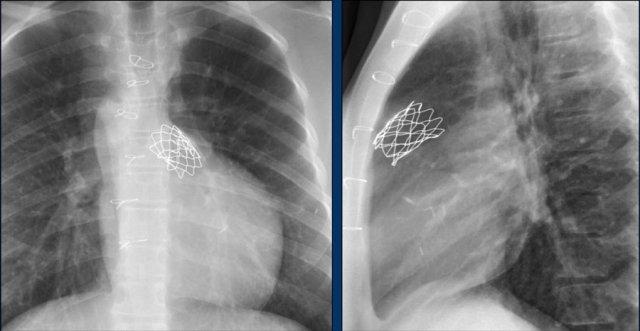

Đây là một bệnh nhân khác mắc hội chứng Twiddler.

Lưu ý hình ảnh điện cực bị cuộn xoắn gần máy tạo nhịp và tại đầu điện cực trong thất phải (mũi tên).